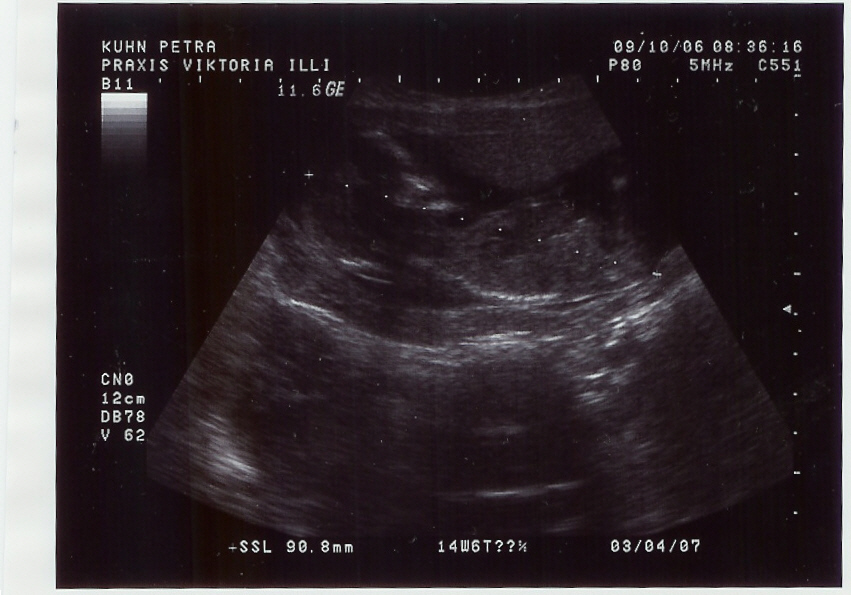

@all Mir geht es so weit gut. Der Bauch wächst und bald habe ich den nächsten Meilenstein 24+0 erreicht. Nächsten Montag habe ich nächsten Termin.